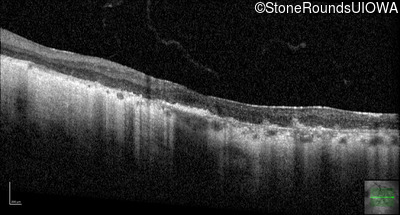

Optical Coherence Tomography - Right - 20/150

Exemplar / OCT Stack

OCT Stack

Optical Coherence Tomography - Left - 20/100 +1